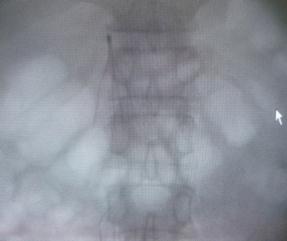

以下是下腔静脉滤器置入及左下肢深静脉置管溶栓术治疗前后对比图

下腔静脉滤器置入

左下肢深静脉置管溶栓术前 左下肢深静脉置管溶栓术后